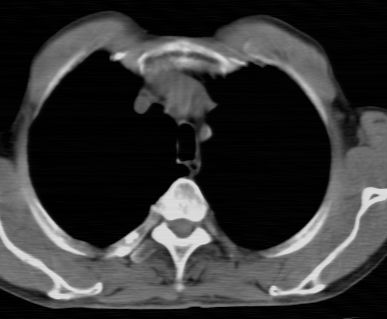

标题: CT24783:m71,既往肺心病史3年,现咳嗽,憋喘。 [打印本页]

标题: CT24783:m71,既往肺心病史3年,现咳嗽,憋喘。

1、左肺上叶spn,毛刺+分叶+血管集束征,考虑周围型肺癌可能性大

2、全小叶性肺气肿。

1)左肺上叶周围型肺癌可能。2)两肺全小叶型肺气肿。

左上周围型肺癌,全小叶型肺气肿。